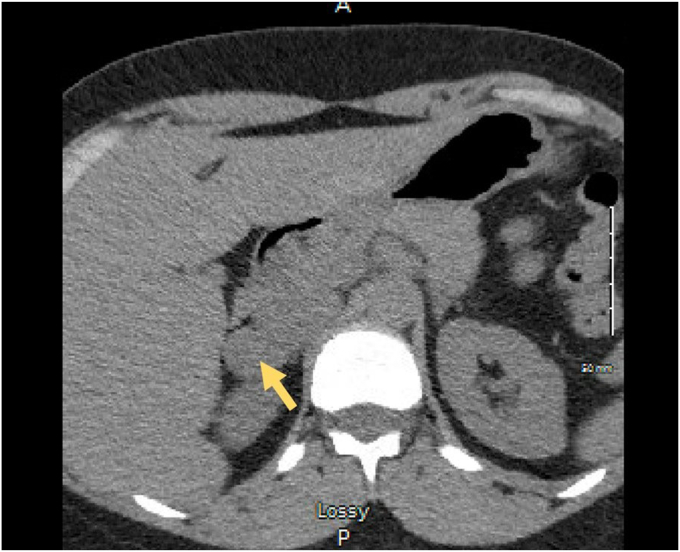

Patient 1 and patient 2 were 35-year-old and 45-year-old woman, respectively. Patient 1 presented with a history of controlled hypertension and symptoms of anxiety along with palpitations, diaphoresis, and flushing. Patient 2 complained of abdominal pain and underwent abdominal computed tomography (CT) imaging. Patient 1 and patient 2 had metanephrine levels of 76 pg/mL and 61 pg/mL (normal <57 pg/mL), respectively, and normetanephrine levels of 161 pg/mL and 116 pg/mL (normal < 148 pg/mL), respectively. CT scans depicted right adrenal masses in both cases: patient 1 had a 2.3 × 2.6 cm mass measuring 36 Hounsfield units on noncontrast CT imaging and patient 2 had a 4.5 × 3.5 cm right adrenal mass measuring 73 Hounsfield units on contrast CT imaging. Both patients underwent laparoscopic robotic adrenalectomies without complications. The pathologic analyses of both cases revealed composite pheochromocytoma-ganglioneuroma tumors. Surveillance at 1 year in both patients demonstrated no evidence of recurrence.